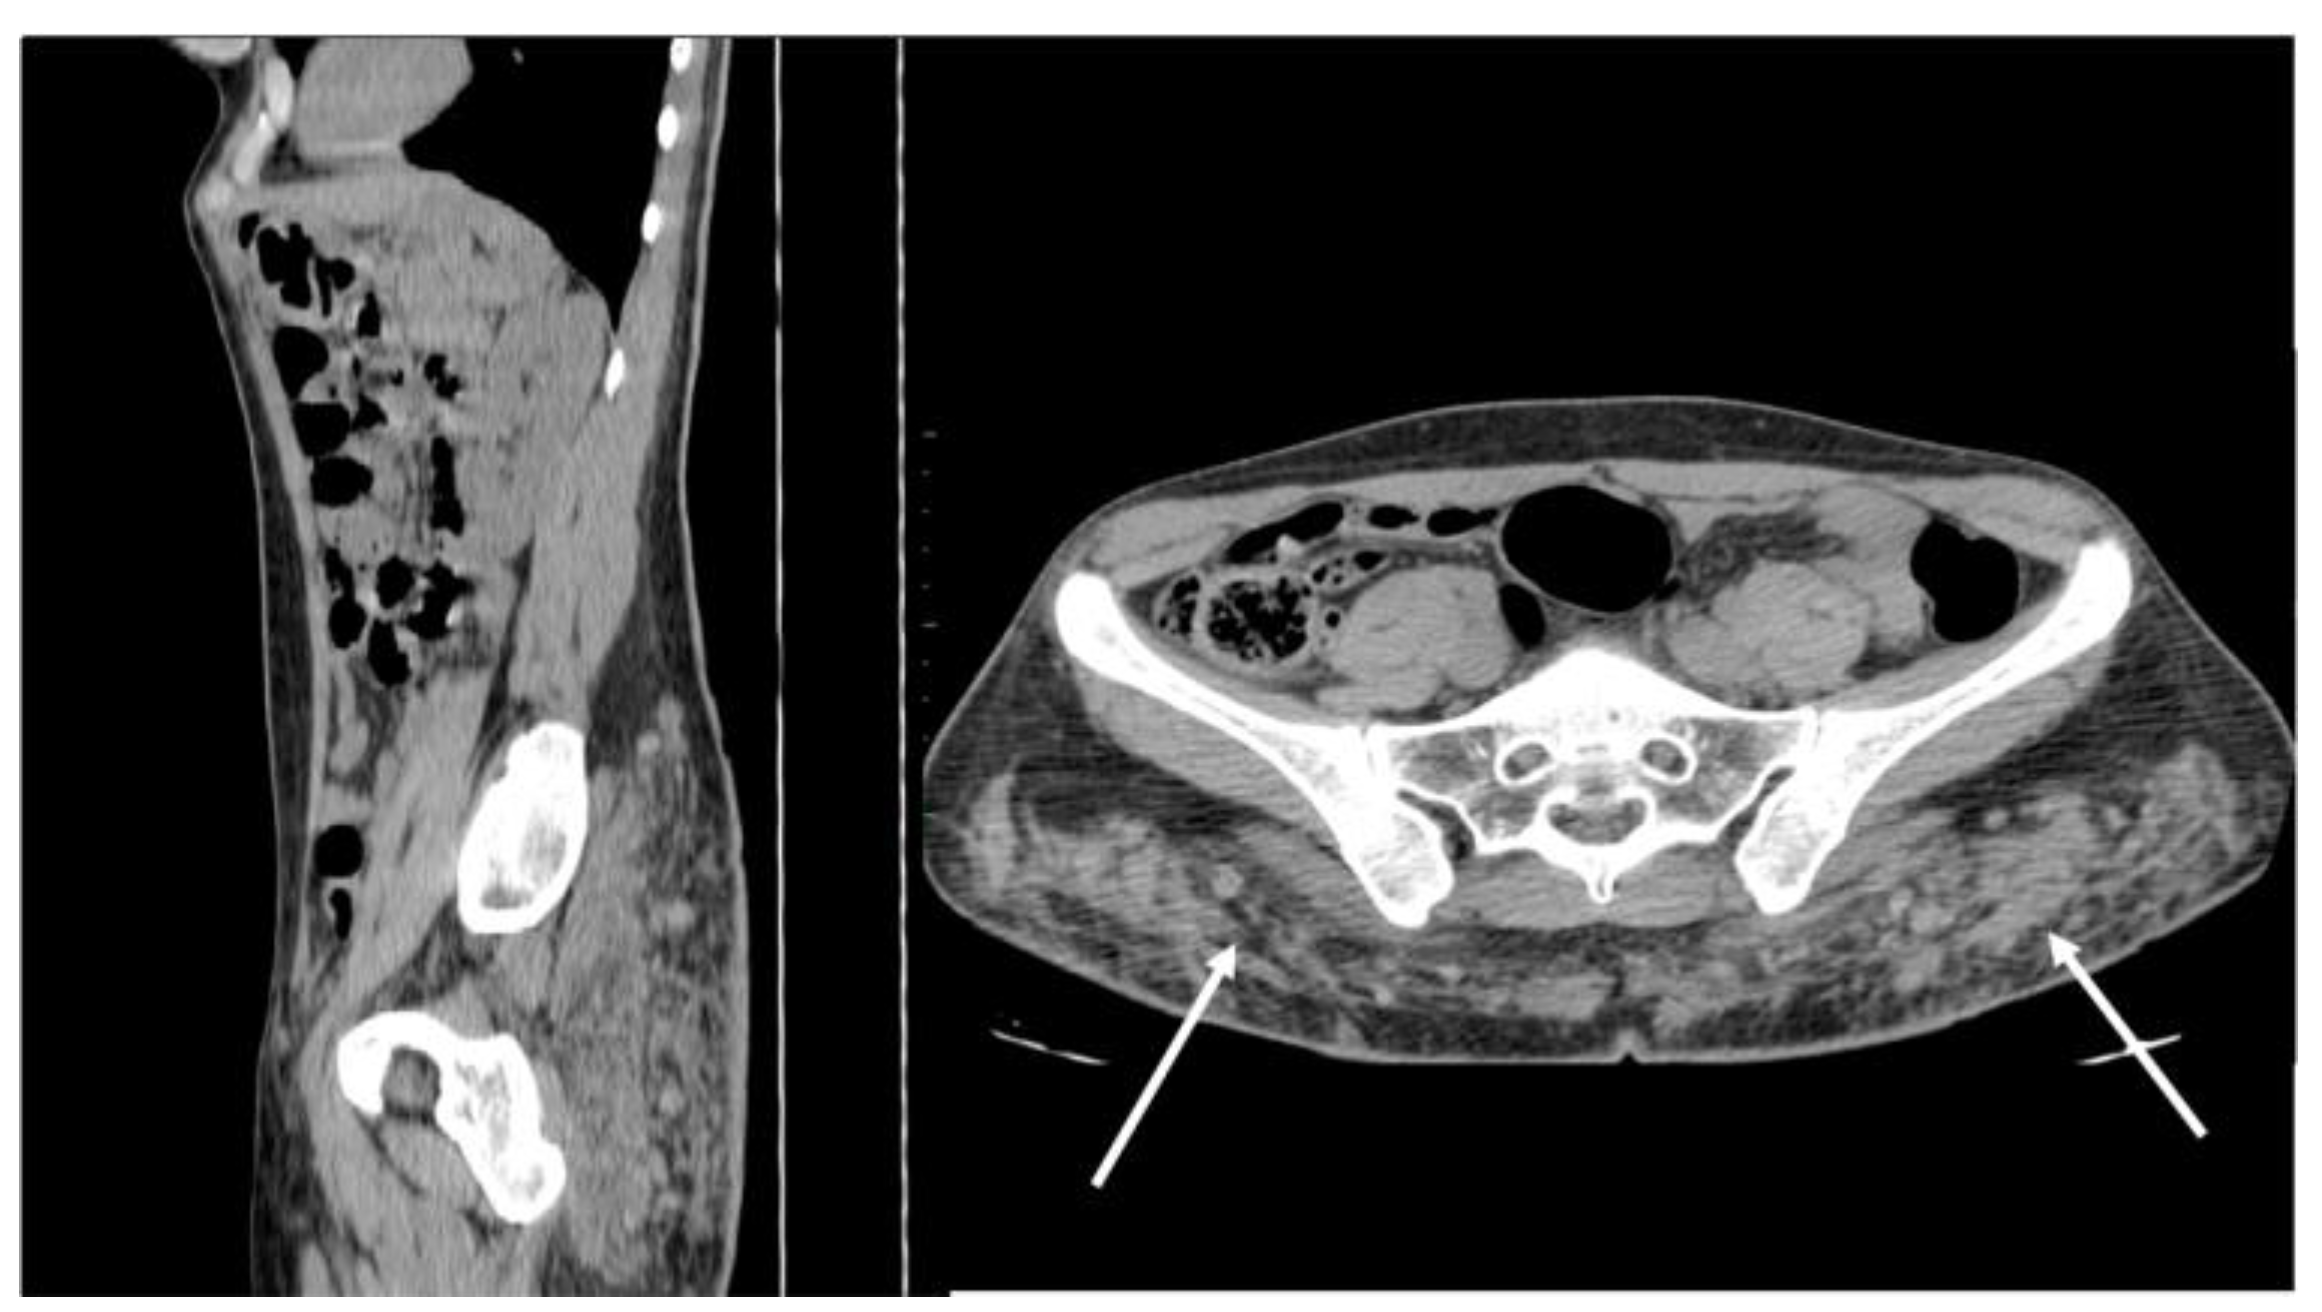

Figure 13. Non-enhanced sagittal and axial CT scan demonstrates free silicon material scattered with an infiltrative appearance, expanding all along the subcutaneous fat of the posterior abdominal wall (arrows). Strand-like lesions coexist with nodular and plaque-like areas, making the differential diagnosis with neoplastic conditions difficult.

Free silicone and paraffin are seen as irregularly scattered collections extended along fascial planes, mimicking sarcomatous or metastatic processes [38,39].

On US, they are heterogeneously echoic, with marked posterior acoustic shadowing [39]. On CT, their diffuse infiltrating appearance is well seen, with solid density but a lack of contrast uptake, accompanied by fat stranding [37,38] (Figure 13).